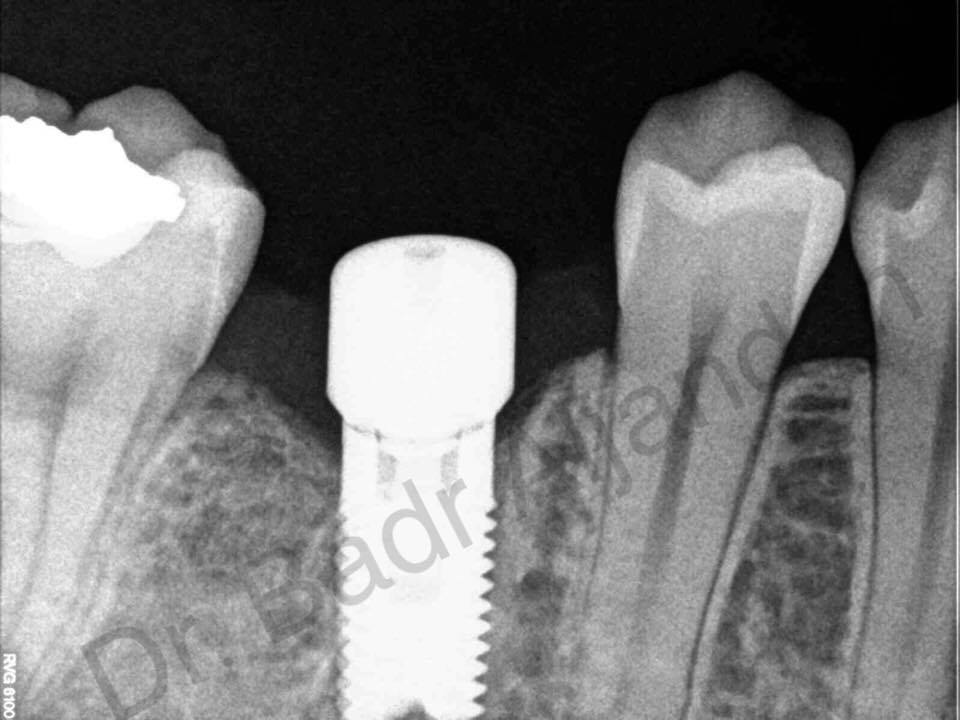

غرسات الأسنان مصنوعة من مادة التيتانيوم. توضع داخل عظام الفك في نفس مكان الأسنان المفقودة. الجزء المعدني الموجود داخل عظام الفك يعمل كوتد بديلا لجذر الأسنان. يتم تركيب الجزء المعدني بواسطة عملية جراحية داخل الفك. وبعد فترة يتم ترابط عظام الفك مع الجزء التيتانيوم مسببا تثبيت قوي للجزء الصناعي داخل الفك. الجزء الأوسط يثبت وتد قوي للأسنان الصناعية.

عند فقدان لسن واحد من المعتاد أن يستعمل تعويض فردي. كل سن صناعي يرتبط بالغرسة الخاصة بها. ممكن استعمال كباري ثابتة و دعامات تستبدل سنتان أو اكثر وتحتاج فقط لعدد 2 أو 3 غرسات (طقم اسنان جزئ). استعمال طقم أسنان كامل (كوبري ثابت) يستبدل كل الأسنان في الفك العلوي أو الفك السفلي. عدد الغرسات تتراوح معتمدة على نوع الاستعاضة الكاملة (متحرك،ثابت). ممكن استعمال طقم متحرك (فوق الطقم) يستند على دعامات في الفك مثل العمود أو الكرة والتجويف ولكن الاستعاضة الثابتة يتم تثبيتها ورفعها بمعرفة الطبيب (طبيب الأسنان).